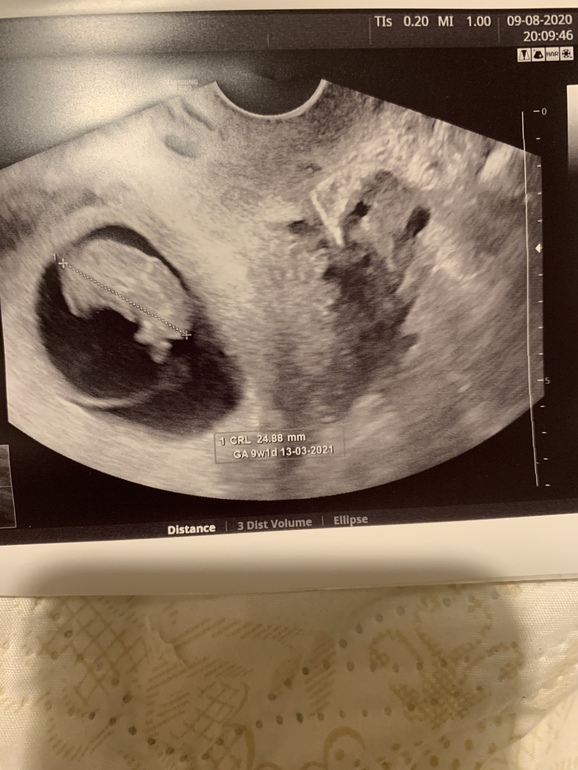

9+1 по узи

Девочки была на узи , Слава Богу Слава Богу услышали сердечко моего малыша 💙💙💙🙏🏻🙏🏻🙏🏻🙏🏻🙏🏻Господи как же я боялась что скажет что замершая , как в январе . Врач сказала все отлично отличный малыш отлично растёт .

Срок по узи 9+1 . . Назначила аскорутин и утрожестан до 13 недель, утром и вечером по 2 таблетки Сказала очень маленькая гематома есть , на всякий случай назначила поддержку , чему я рада , лучше застраховаться .